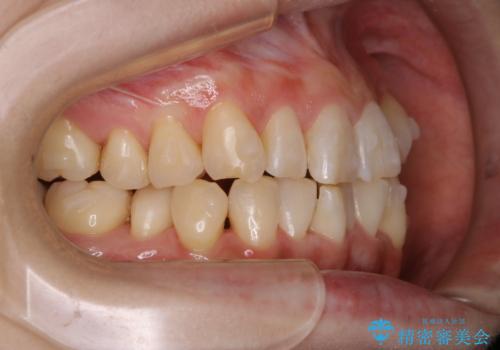

インビザラインでのマウスピース矯正中に歯を白くしたい

- インビザラインでのマウスピース矯正中に、歯の黄ばみが気になるため綺麗に白くしたいとのことでした。PMTC60分コースを行いました。

PMTC(保険外治療)は、毎日の歯磨きで落としきれない汚れや、コーヒ、紅茶・タバコのヤニなどの着色も除去します。目には見えない歯と歯の間・歯肉の境目・インビザライン中はアタッチメント周囲などに残っているプラーク(歯垢)もしっかり取り除きます。PMTCでは専門的な機械や材料を使用して、徹底的に汚れを除去するため、虫歯・歯周病・口臭予防などにつながります。